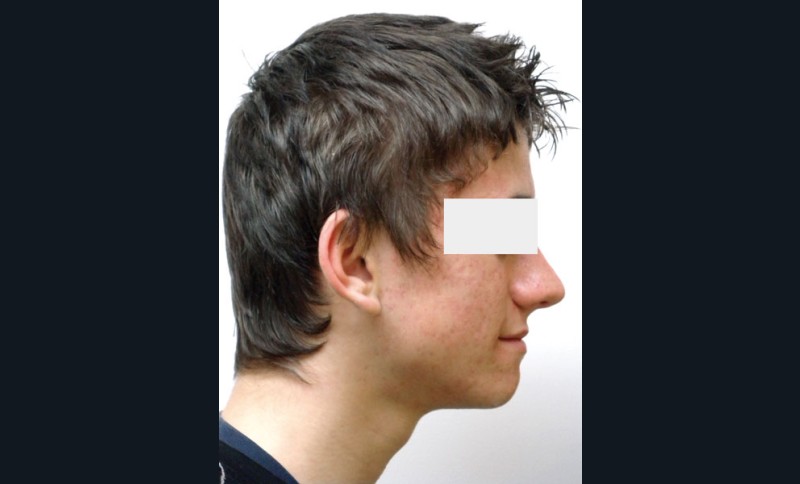

Guillaume, 14 ans, se présente pour la première fois en consultation d’orthodontie, adressé par son dentiste. Il se plaint de la position de ses canines.